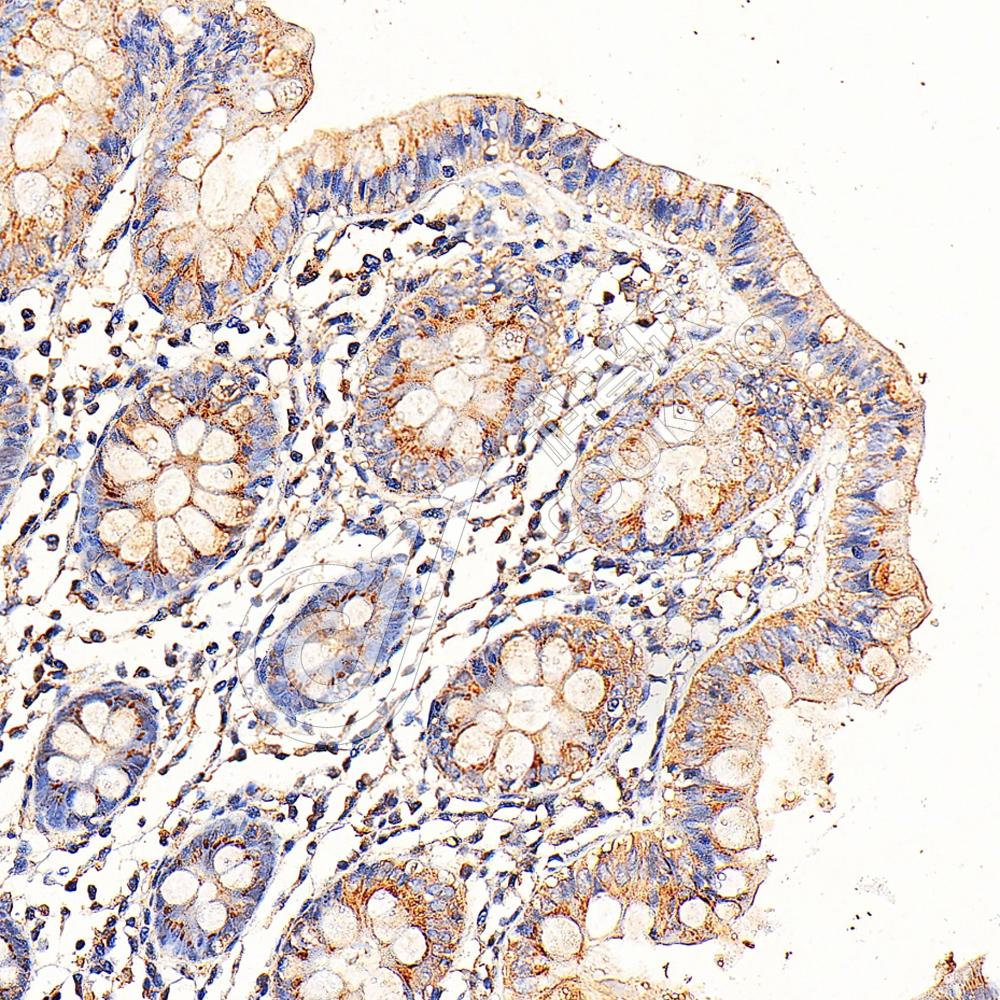

IHC检测IL-10蛋白(货号 K133324).

样品: 小鼠脾, 4%多聚甲醛 (货号KSG1101) 固定12-24小时.

抗原修复: 柠檬酸抗原修复液(干粉, pH 6.0) (KSG1201), 98℃, 20分钟.

—抗: 1: 600稀释, 4℃ 孵育过夜.

二抗: S-vision免疫组化多聚二抗(山羊抗兔),即用型 (货号KB3906), 室温孵育20分钟.